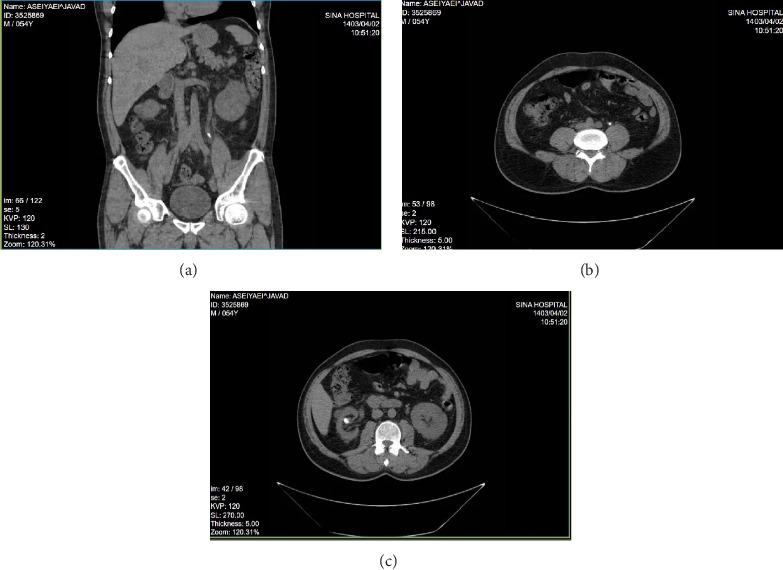

双J (DJ)支架置入术相关的并发症有很好的文献记载,但DJ支架打结仍然是一个极其罕见的事件。我们提出了一个独特的情况下,一个打结和结壳的DJ支架,以及对这一罕见并发症的文献回顾。一名55岁男性,因结石导致输尿管梗阻,最初采用经皮肾造口术(PCN)和DJ支架置入术。患者出现在支架移除的延迟随访后。尽管成像显示没有结痂或打结的证据,膀胱镜尝试移除支架失败。进一步的评估,包括输尿管镜检查,发现DJ支架在肾盂处有明显的结痂和打结。使用半刚性输尿管镜和碎石成功取出支架,无需开放手术。该病例强调了早期随访和患者依从性对预防此类并发症的重要性。当单纯牵引不能取出DJ支架时,应采用先进的内镜技术,如碎石和输尿管镜检查,以有效地处理复杂病例。

Complications related to double J (DJ) stent placement are well documented, but DJ stent knotting remains an exceedingly rare event. We present a unique case of a knotted and encrusted DJ stent, alongside a review of the literature on this rare complication. A 55-year-old man with a history of ureteral obstruction due to stones was managed initially with percutaneous nephrostomy (PCN) and DJ stent placement. The patient presented after a delayed follow-up for stent removal. Despite imaging showing no evidence of encrustation or knotting, cystoscopic attempts to remove the stent failed. Further evaluation, including ureteroscopy, revealed significant encrustation and knotting of the DJ stent at the renal pelvis. The stent was successfully removed using a semirigid ureteroscope and lithoclast without open surgery. This case highlights the importance of early follow-up and patient compliance in preventing such complications. When simple traction fails to remove a DJ stent, advanced endoscopic techniques such as lithotripsy and ureteroscopy should be employed to manage complex cases effectively.